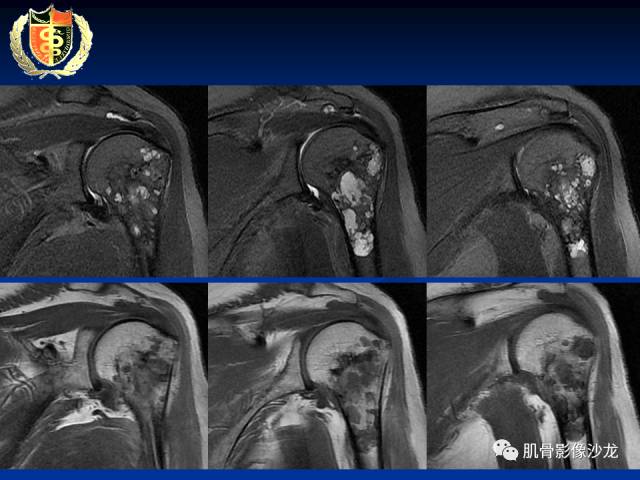

骨淋巴瘤及软骨肉瘤两例CT及MR影像表现

各位老师,磁共振图像是增强检查,最后一张是DWI图像[愉快]

胫骨近端骨质破坏,边缘不清,破坏边模糊,骨皮质不完整,可见软组织肿块突破骨皮质外,病灶累及关节面下,无关节内累及,MRI病灶呈T2WI高信号,信号均匀,考虑:恶性肿瘤性病变,淋巴瘤先考虑,转移瘤及其他待排

淋巴瘤弥散不受限吧

受限

骨的基本形态保留的恶性肿瘤基本上也就尤文和淋巴瘤了

这俩年龄相差悬殊,所以比较容易鉴别

内部密度和信号比较均匀,无钙化,无骨膜反应,骨质破坏边缘不清晰,软组织较明显,弥散受限,首先不能排除淋巴瘤